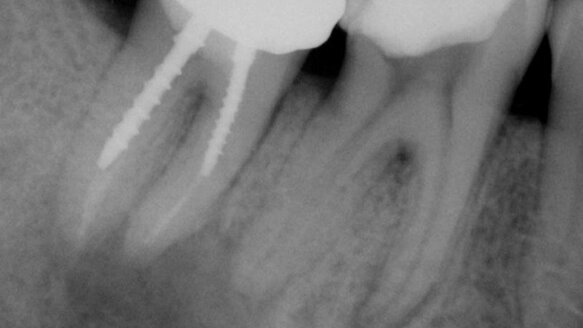

Cone-beam radiography helps me to avoid potential unwelcomed surprises during surgery. For example, one patient came to me with persistent swelling. While the post-op 2-D PA image showed healing (Figs. 1a and 1b), the cone-beam scan showed an area of very large infection extending to the inferior alveolar nerve with extensive cortical bone destruction (Fig. 2). This was vital pre-surgical information.

With another patient who was suffering from intense pain from a tooth that was heavily restored with a very large periapical rarification, I decided to do an apicoectomy to provide immediate relief. On a 2-D X-ray, all appeared to be simple (Fig. 3); however, because the problem was on a posterior tooth, I decided for safety sake to acquire a CBCT scan.

The 3-D view showed that the infection was so far in lingually (Fig. 4) that a very thick layer of cortical bone had to be removed, and the positioning of the inferior alveolar nerve was so coronal that paresthesia could also have resulted in this case.